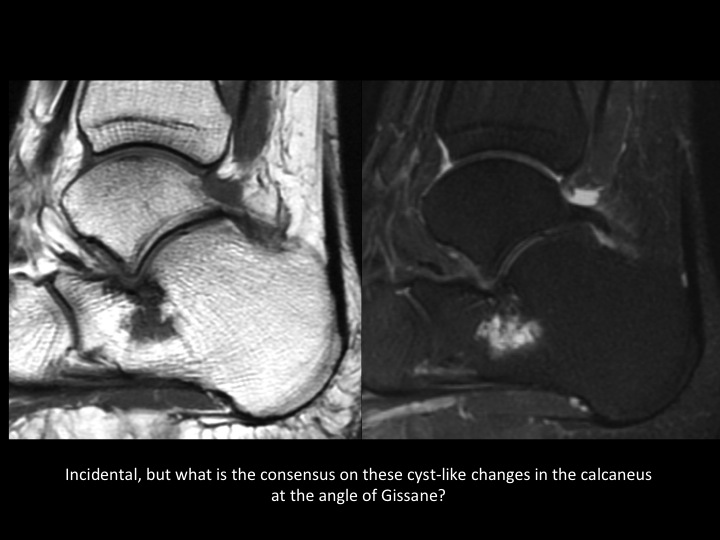

There is an accessory articular facet of the medial talus posterior to the middle facet, with non-osseous extra-articular talocalcaneal coalition (slides 1-2). In slide 3 there is an accessory ligament Ive not seen connecting the lateral tubercle of the posterior talar process and the posterior calcaneal tubercle, with surrounding synovitis (slide 4); does this have a name? As a side question, is there a consensus as to what the cyst-like changes are deep to the angle of Gissane in the calcaneus? Do you all report this? I consider this incidental, does anyone disagree?